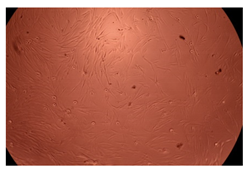

The results of the cytotoxicity assay, given in Figure 5, indicate that the tested PMs at all three established concentrations (10, 50, and 100 µg/mL) did not show cytotoxic effects on fibroblast cells at either 24 or 48 h after incubation. The percentages of cell viability were high, over 90%, in cells that were exposed to a concentration of 10 µg/mL for 24 h for all tested materials. Even at 48 h after incubation, the percentage of cell viability was as high as 90.4% in cells exposed to a concentration of 10 µg/mL for the Cop B sample. For both drug-loaded PMs, the cell viability decreased slightly at all tested concentrations. It also appears that the Dorzolamide-loaded PMs have slightly lower cell viability as compared to IMC-loaded PMs. Micrographs of the fibroblast cells after incubation times of 24 and 48 h are provided in Table 2.

Table 2.

Micrographs of fibroblast cells after 24 and 48 h incubation times, respectively.

As the cell viability values are all over 80%, the results indicate that the PMs, at the established concentrations, can be used successfully for in vivo biomedical applications.